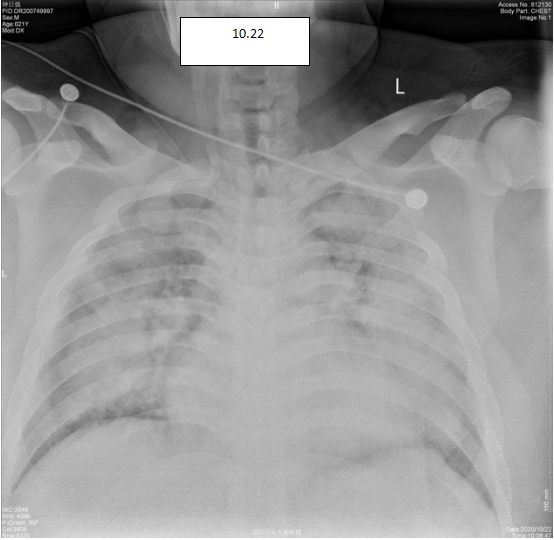

病例回顾  该患者是一位21岁的青年男性,体重170公斤,因“反复咳嗽咳痰气促4天,加重1天”入院。入院后8时后气促明显,无尿,氧合指数<100mmHg,床边胸片提示肺渗出明显。患者体型肥胖,深静脉穿刺难度高,由科室钟国荣副主任医师亲自为患者放置锁骨下静脉穿刺管及股静脉穿刺管,在莫俊德主任医师的指挥下,迅速对该患者采用创新性体外二氧化碳清除联合CRRT、呼吸机辅助通气、俯卧位通气、抗感染等治疗。